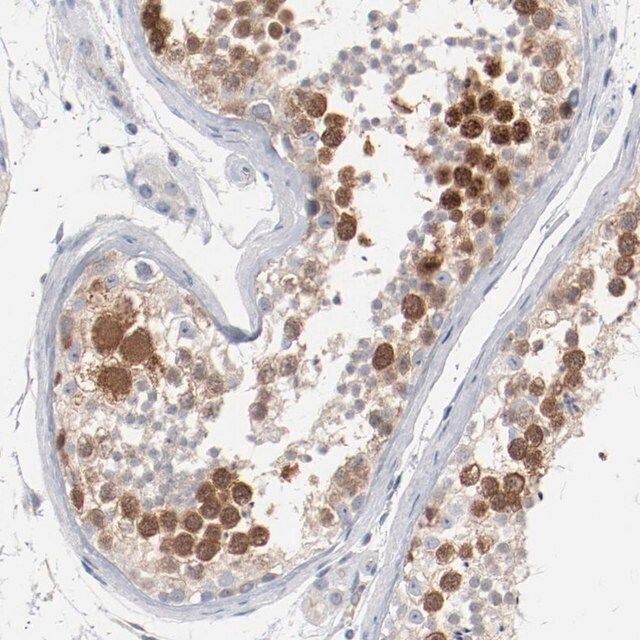

Anti-CDK1 antibody produced in rabbit, a Prestige Antibody, is developed and validated by the Human Protein Atlas (HPA) project (www.proteinatlas.org). Each antibody is tested by immunohistochemistry against hundreds of normal and disease tissues. These images can be viewed on the Human Protein Atlas (HPA) site by clicking on the Image Gallery link. The antibodies are also tested using immunofluorescence and western blotting. To view these protocols and other useful information about Prestige Antibodies and the HPA, visit sigma.com/prestige.

- IHC tissue array of 44 normal human tissues and 20 of the most common cancer type tissues.